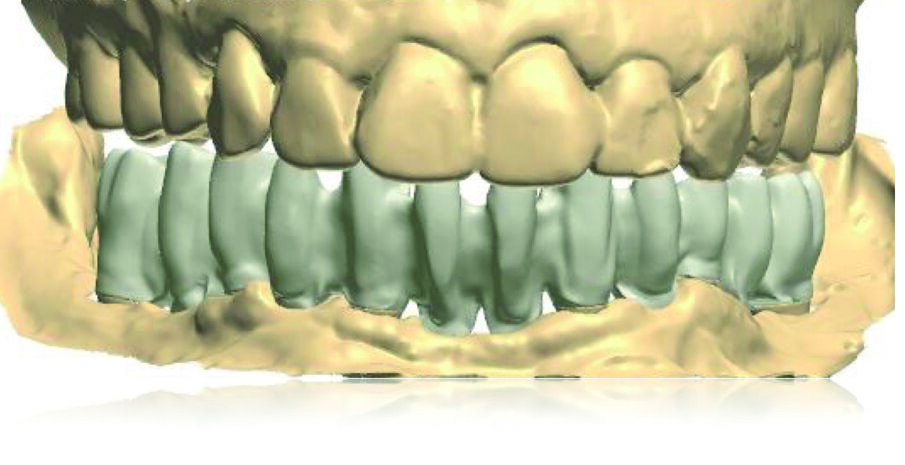

I nuovi modelli master sono stati montati in articolatore in accordo alle procedure di cross-mounting al fine di replicare dimensione verticale, rapporti sagittali tra mascella e mandibola, contatti occlusali, ingombro delle protesi e parametri estetici (Figg. 12, 13). La struttura della protesi inferiore è stata progettata al CAD ed è stata realizzata al CAM fresando un blocco in cromo-cobalto che è stata poi ceramizzata (Figg. 14-16).